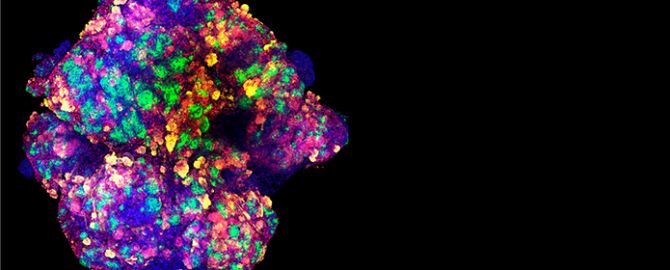

Imagen al microscopio de un organoide de riñón generado in vitro a partir de células madre humanas. (Foto: Cima)

Un paso previo a la experimentación con el fármaco es el conocimiento de la interacción entre el virus y la célula humana. Para agilizar el proceso de investigación y llevar los posibles resultados cuanto antes a la clínica, los investigadores han empleado miniriñones u organoides de riñón infectados con SARS-CoV-2. Mediante la caracterización de estas réplicas de riñón humano, “hemos conseguido identificar las células del tejido renal que expresan la enzima ACE2, un receptor que utiliza el virus para entrar en las células humanas”, señala el Dr. Felipe Prosper, director del Programa de Medicina Regenerativa del Cima y participante en la investigación.